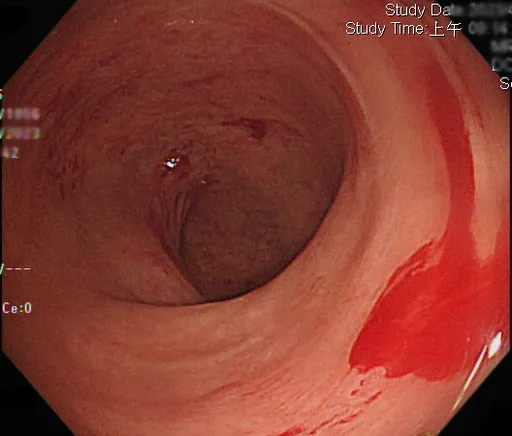

...的小血管可能會擴張扭曲,形成微小的動靜脈吻合,倘有慢性腎病會讓血管異常增生提早發生。 大便顏色不同...